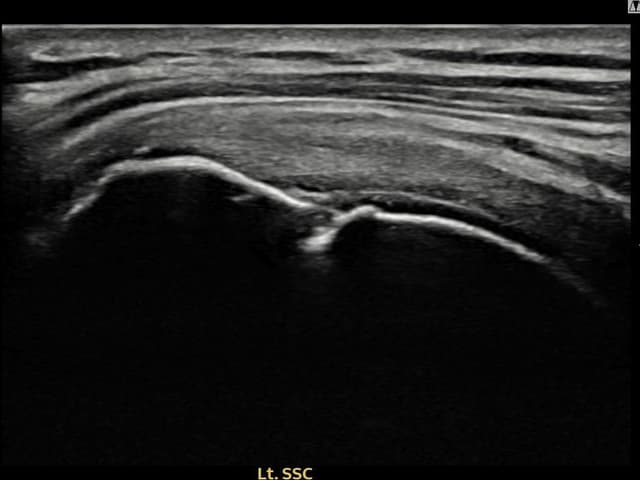

[経過期間: 24.04.09~24.06.17]

[縫縮術] 超音波検査にて左 棘上筋腱 付着部部分断裂(11mm × 4mm (腱厚の約44%欠損))を確認。縫縮術施行後、腱の連続性が回復し、日常生活に復帰されました。

[経過期間: 24.04.26~24.07.05]

[縫縮術] 超音波検査にて右 棘上筋腱 관절면측 광범위 部分断裂(16mm × 5mm (腱厚の約75%欠損))を確認。縫縮術施行後、腱の連続性が回復し、日常生活に復帰されました。